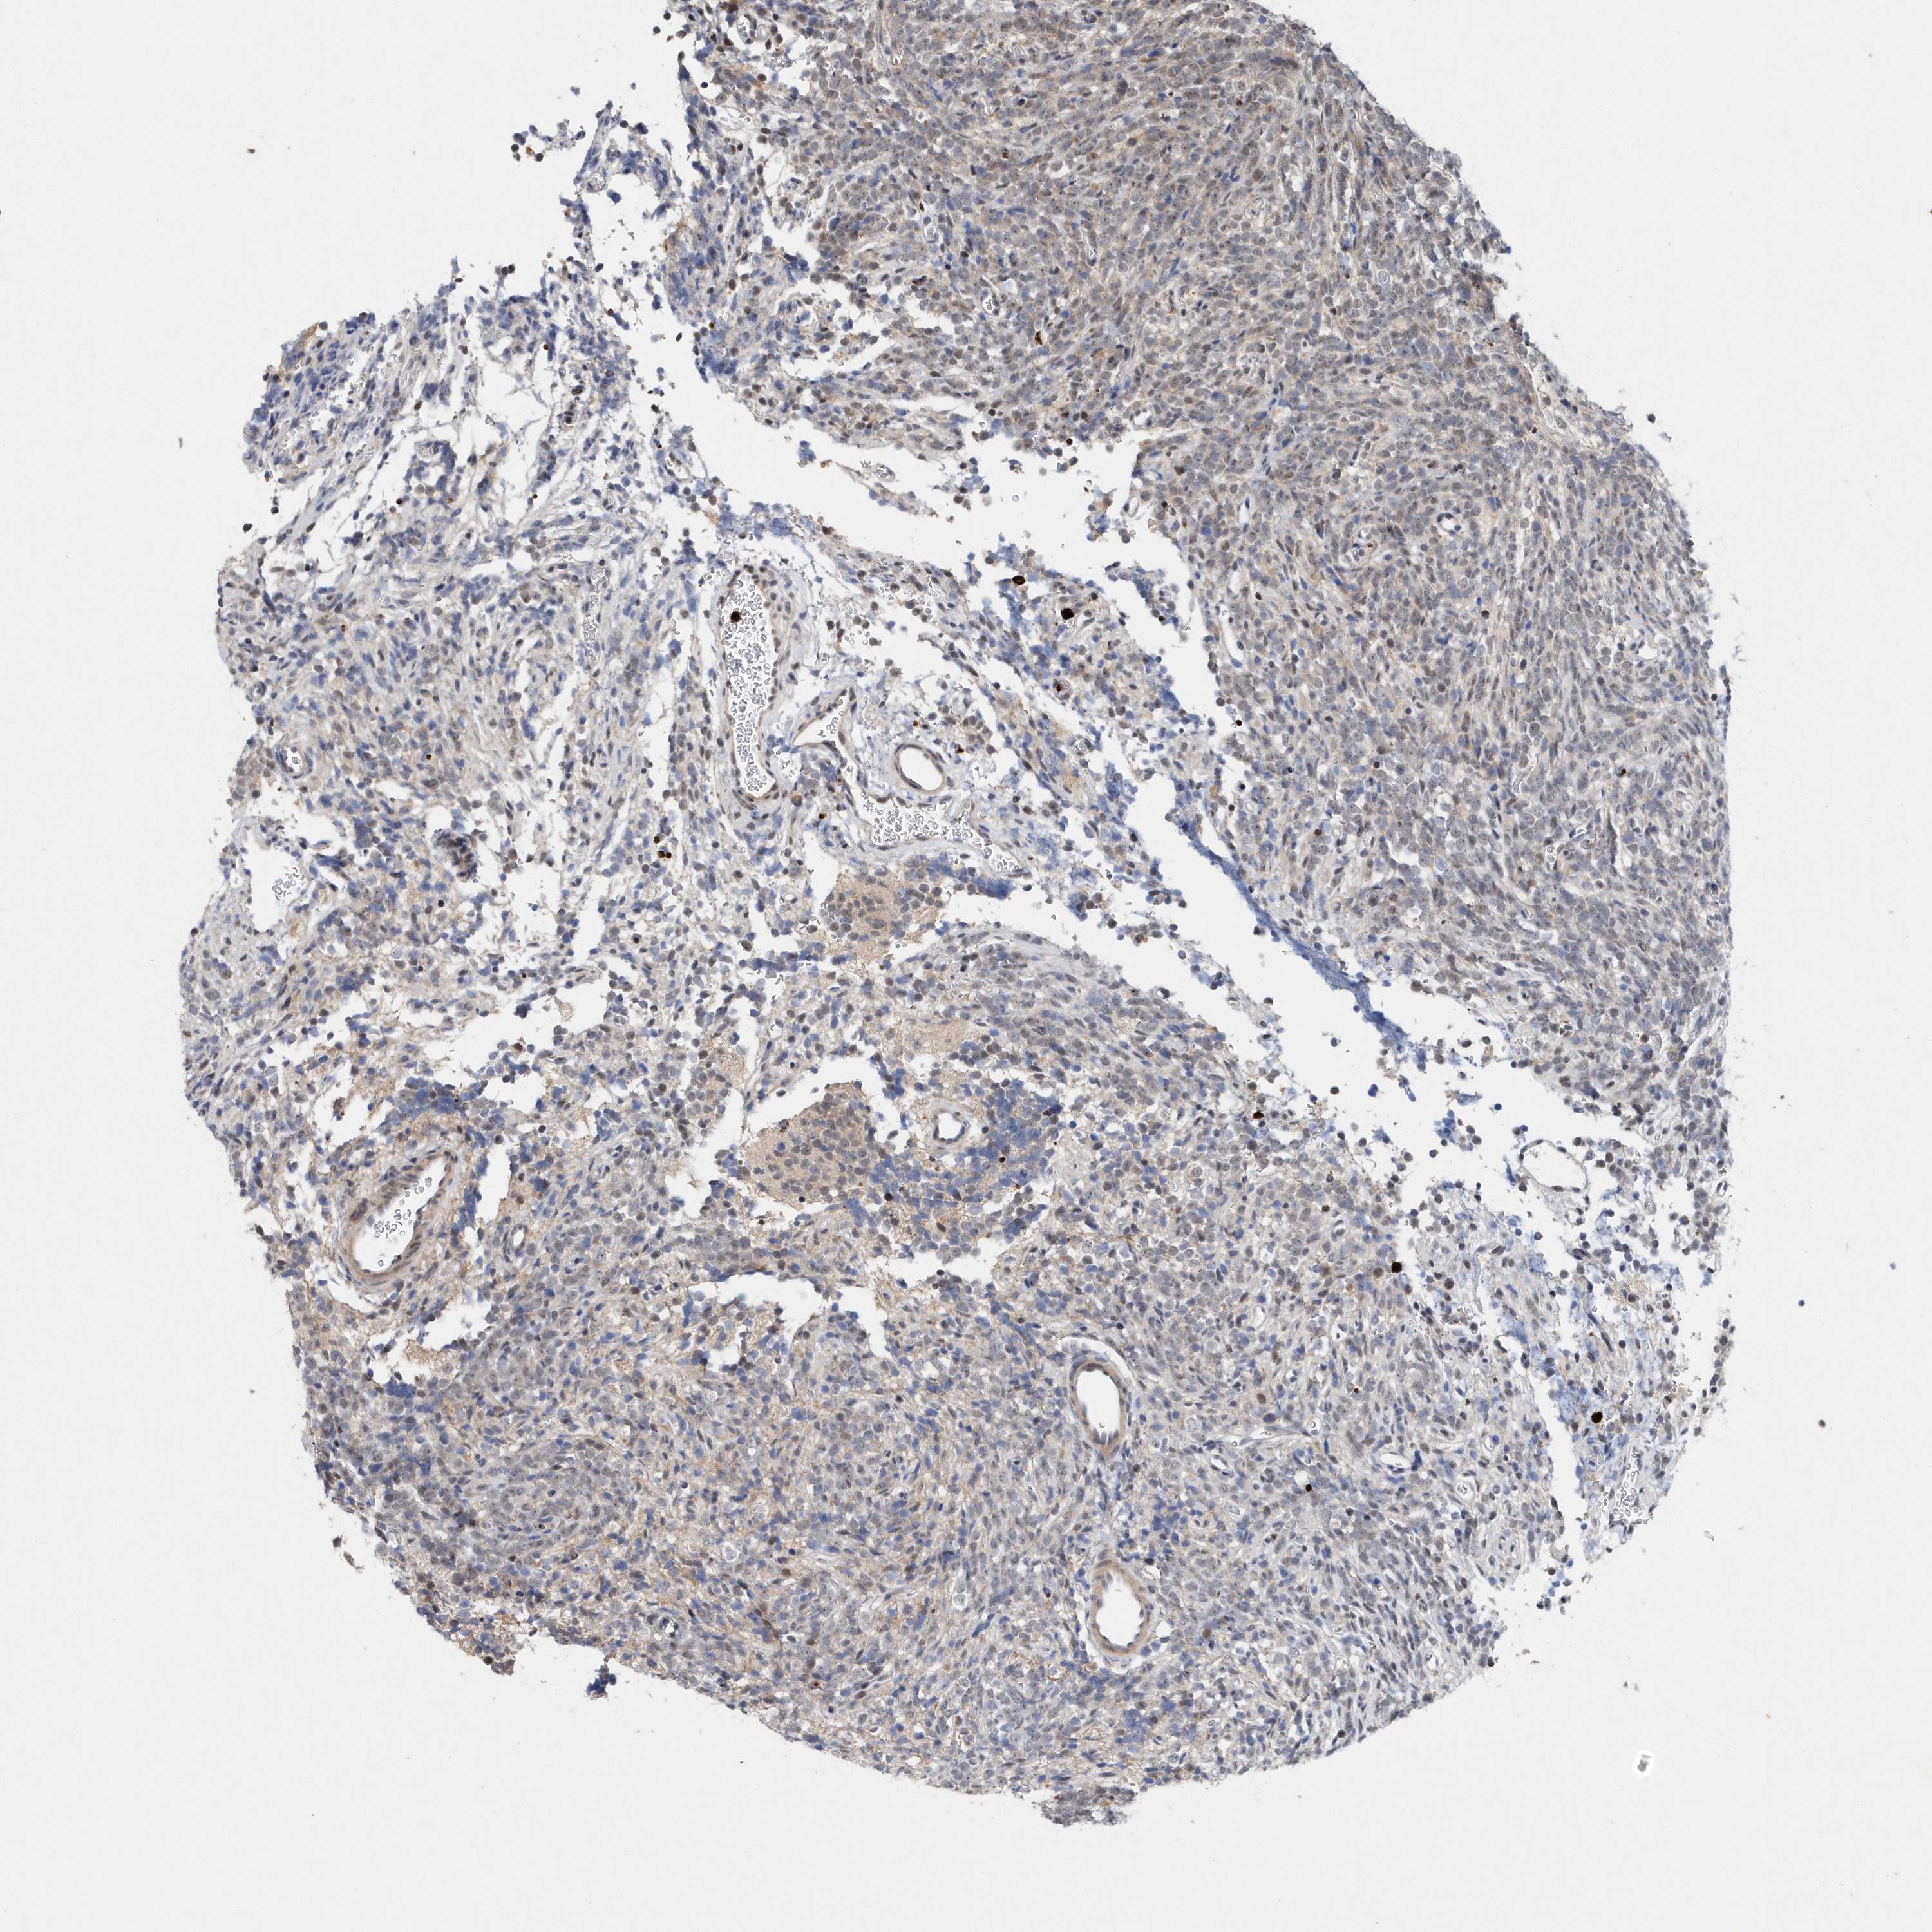

GLIOMA - Protein expressioni

A mouse-over function shows sample information and annotation data. Click on an image to view it in a full screen mode. Samples can be filtered based on level of antibody staining by selecting one or several of the following categories: high, medium, low and not detected. The assay and annotation is described here.

Note that samples used for immunohistochemistry by the Human Protein Atlas do not correspond to samples in the TCGA dataset.

Antibody stainingi

Antibody staining in the annotated cell types in the current human tissue is reported as not detected, low, medium, or high, based on conventional immunohistochemistry profiling in selected tissues. This score is based on the combination of the staining intensity and fraction of stained cells.

Each image is clickable and will lead to virtual microscopy that enables deeper exploration of all samples and also displays staining intensity scores, fraction scores and subcellular localization as well as patient and tissue information for each sample.

Antibody HPA037578

Staining

High

Medium

Low

Not detected

Intensity

Strong

Moderate

Weak

Negative

Quantity

>75%

75%-25%

<25%

None

Location

Nuclear

Cytoplasmic/membranous

Cytoplasmic/membranous,nuclear

Glioma, malignant, High grade

Glioma, malignant, Low grade

Glioblastoma, NOS